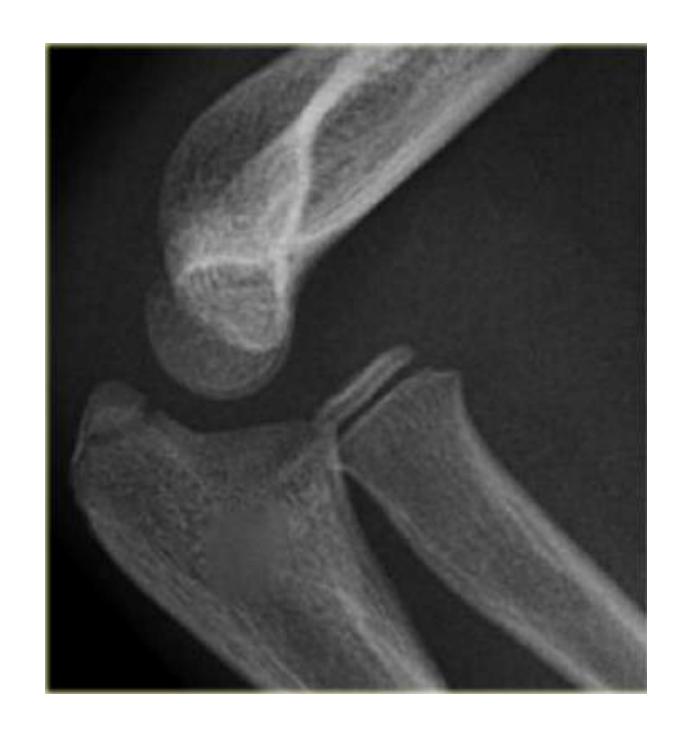

Q8/ What is the type of fracture shown in these pictures?

- A- Salter harris fracture II